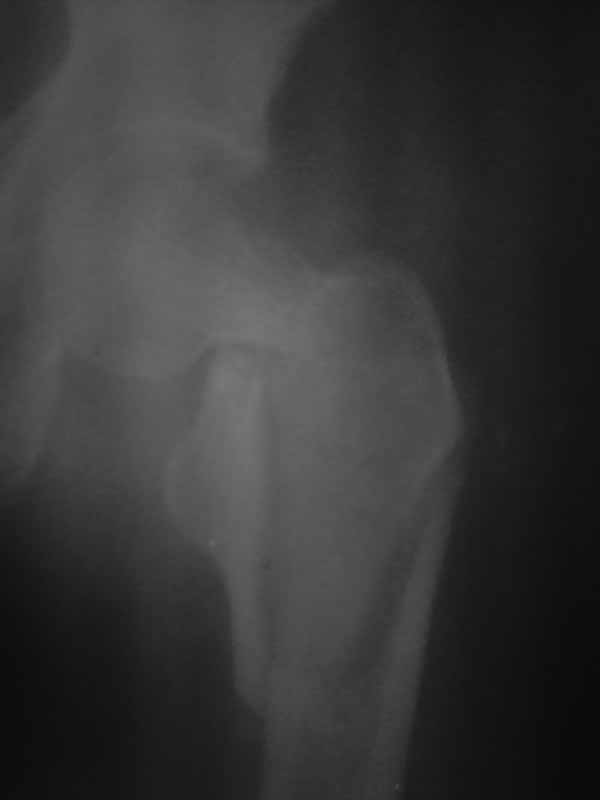

Хотелось услышать дискуссию, по-этому выложил некачественный снимок с вопросом. Стараюсь выложить немного лучше. Гамму она преобрести не сможет. Смущает то что шейка больно хлипкая и винтом развалим ее до конца. На снимке кажется что и фрагмент шейки также сломан вдоль.

Имя     : 3.jpg

Тип     : image/jpg

Размер  : 16487 байтов

Описание: отсутствует

Url     : http://weborto.net:8080/pipermail/ortho/attachments/20111002/91f177e3/attachment-0006.jpg